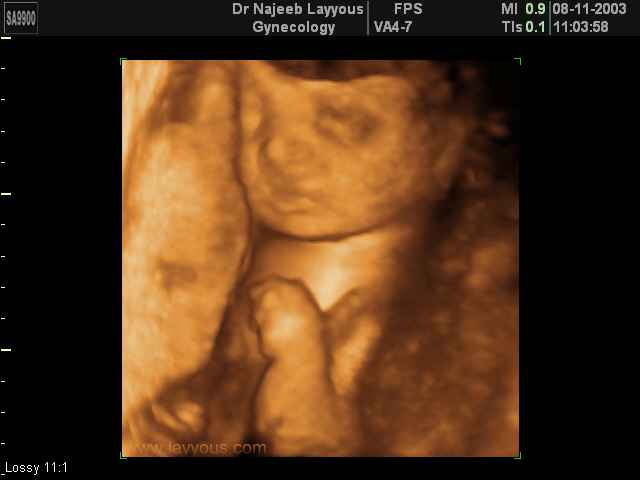

- لقطات فيديو للجنين بجهاز الموجات فوق صوتية رباعي الأبعاد

- صور لأعضاء الجنين

- صور لتصرفات الجنين داخل الرحم